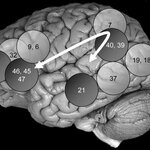

Parieto-Frontal Integration Theory (P-FIT) - A Neural Basis Of Intelligence

A primary mystery puzzling neuroscientists -- where in the brain lies intelligence" -- just may have a unified answer. In a review of 37 imaging studies related to intelligence, including their own, Richard Haier of the University of California, Irvine and Rex Jung of the University of New Mexico have uncovered evidence of a distinct neurobiology of human intelligence. Their Parieto-Frontal Integration Theory (P-FIT) identifies a brain network related to intelligence, one that primarily involves areas in the frontal and the parietal lobes. Their report includes peer commentary from 19…